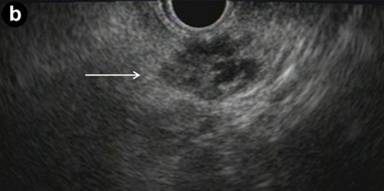

A 35-year-old man presented to the emergency department with complaints of abdominal and back pain after a fall. On axial imaging, a cystic neoplasm of the pancreas was incidentally discovered. The CT scan revealed a 2.1x1.7 cm, well-defined, low-density, non-calcified cystic lesion arising from the pancreatic tail (Figure 1a). The differential diagnosis included pseudocyst, mucinous or serous pancreatic cyst, and malignant pancreatic cyst. The serum tumor markers included normal CEA and CA 19-9; chromogranin A was elevated at 237 ng/mL (reference range: 0-95 ng/mL) and neuron specific enolase was also elevated at 14.2 µg/L (reference range: 3.7-8.9 µg/L). MRI and 18F-FDG-PET were not utilized.

The patient underwent EUS and FNA to further characterize the cyst and guide management recommendations. EUS described an irregular, heterogeneous, complex cyst-like lesion at the tail of pancreas. The cyst did not appear to communicate with the main pancreatic duct and the main pancreatic duct appeared normal. Multiple septations and hypoechoic debris gave a complex cyst appearance (Figure 1b). FNA using a 22 gauge needle retrieved a whitish, necrotic appearing material. CEA and amylase levels could not be determined because no fluid was returned. Cytology of the FNA specimen identified histiocytes, benign epithelial cells and lymphocytes.

Figure 1. a. CT image of pancreatic dermoid cyst (white arrow) demonstrating a well-circumscribed, hypodense lesion. b. EUS revealed a complex cyst (white arrow) in the tail of the pancreas. |